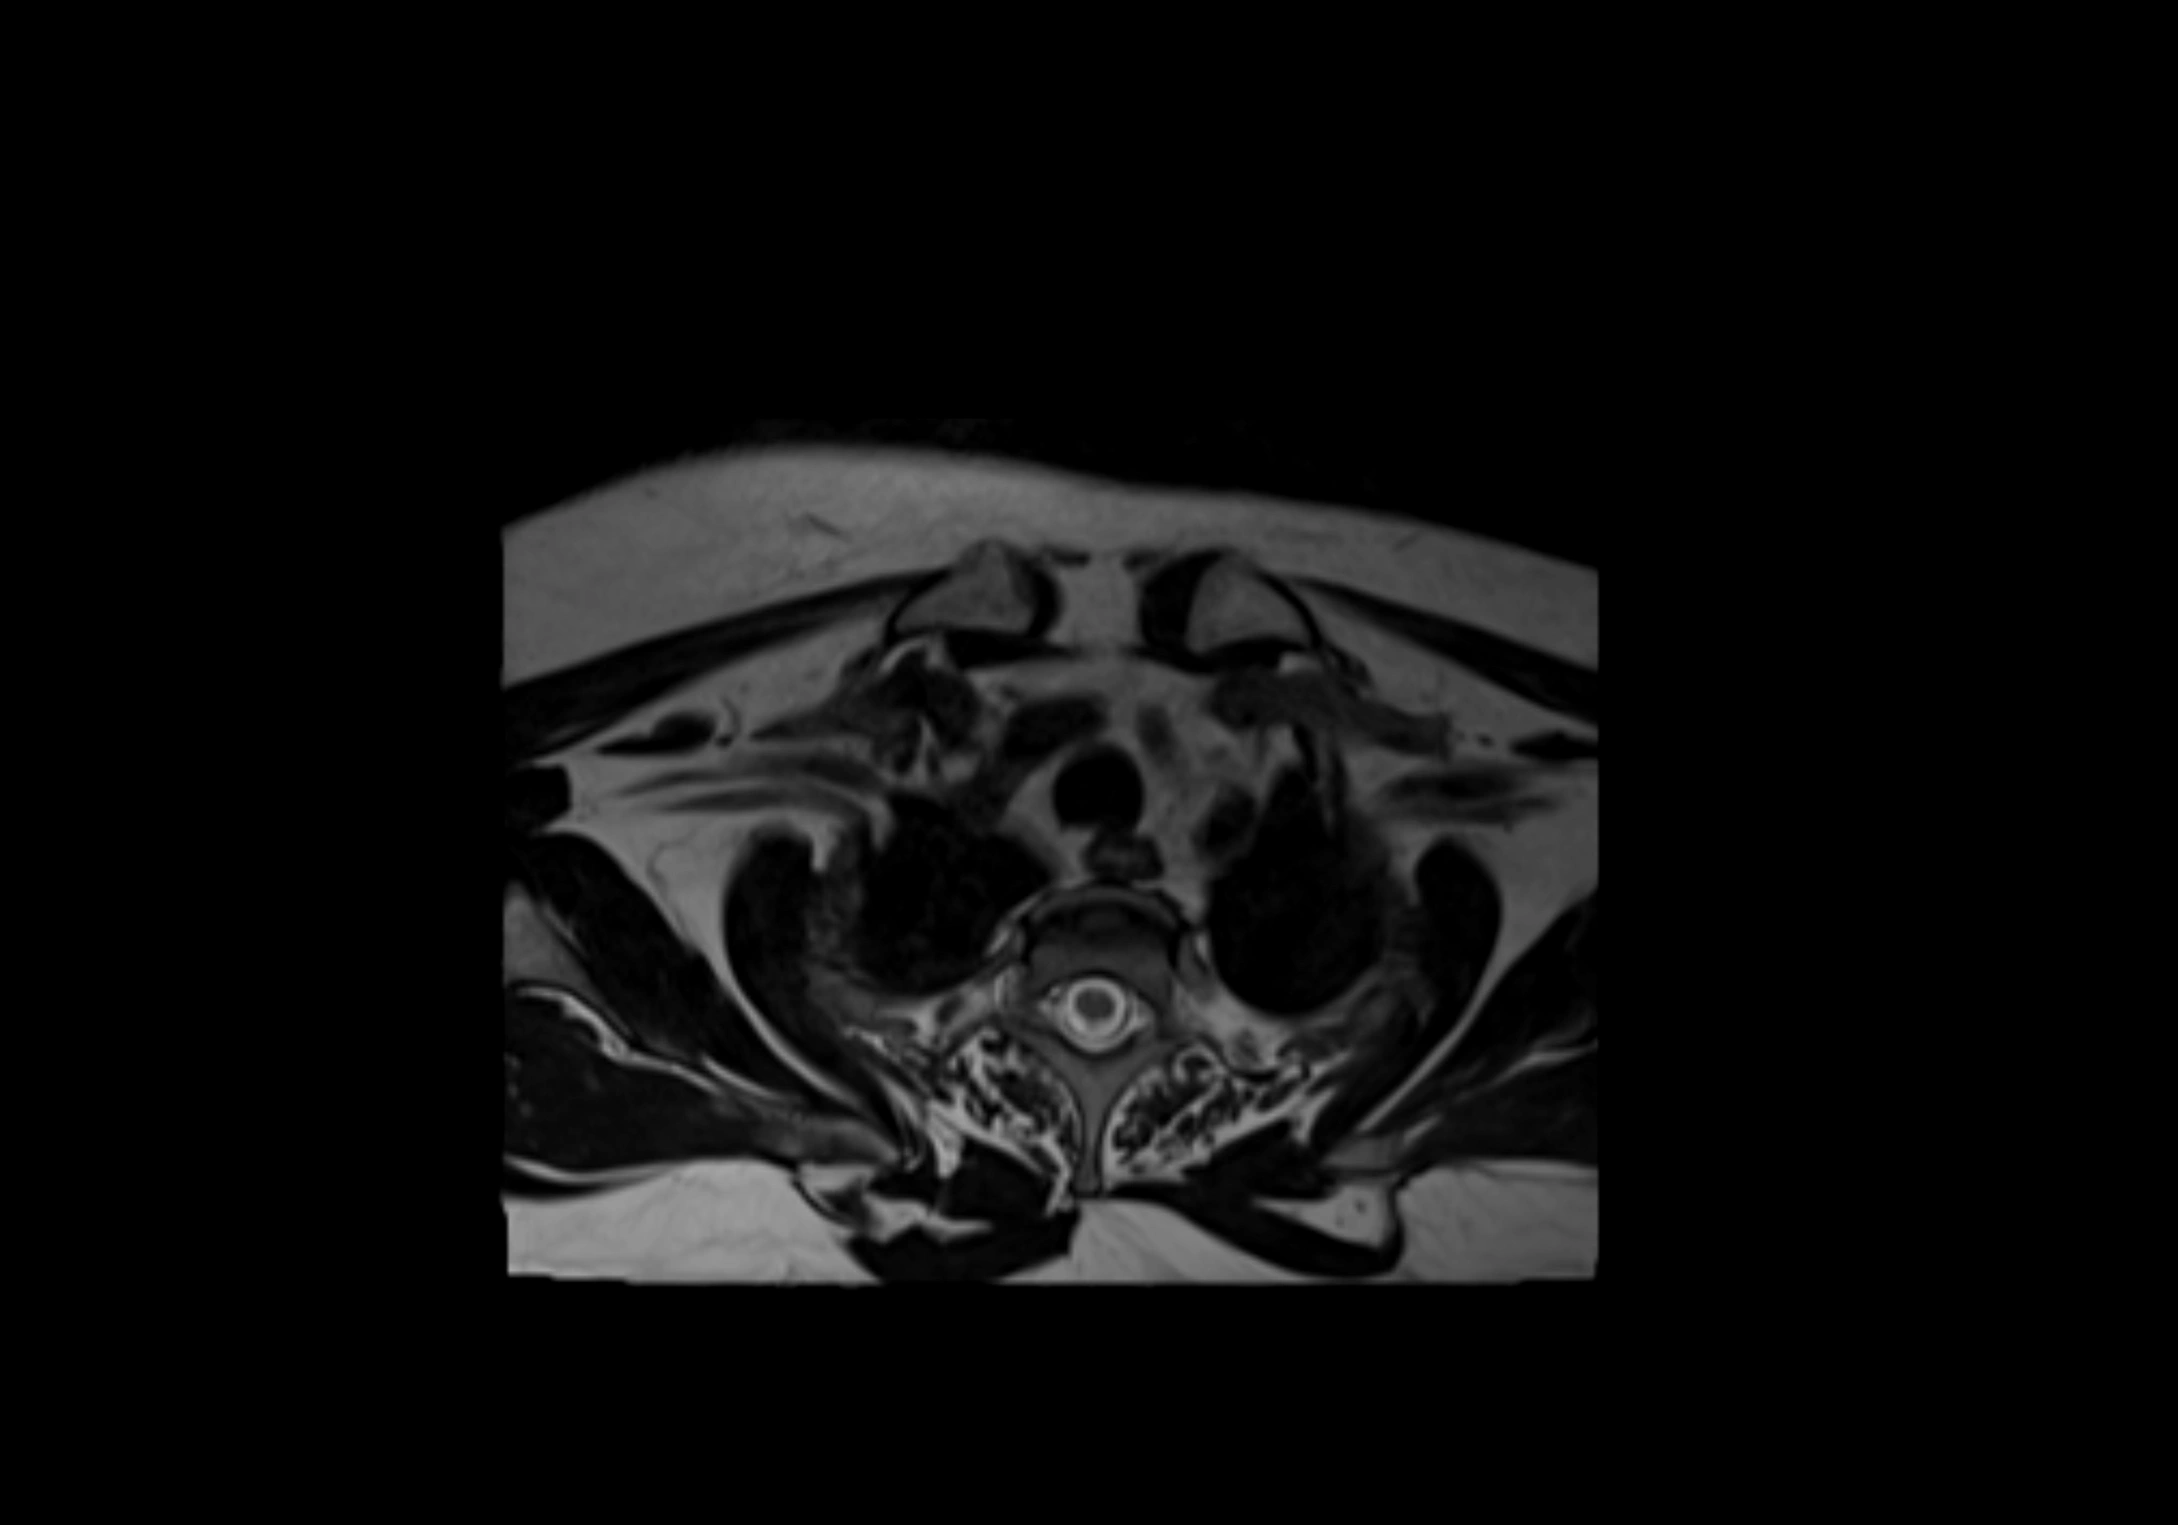

MRI Appearance

STIR (Short Tau Inversion Recovery):

• Fat suppression enhances visualization of edematous or pathological nodes

• Normal nodes appear low to intermediate signal, while inflamed or metastatic nodes appear hyperintense

• Useful for detecting subtle lymphadenopathy or early pathology